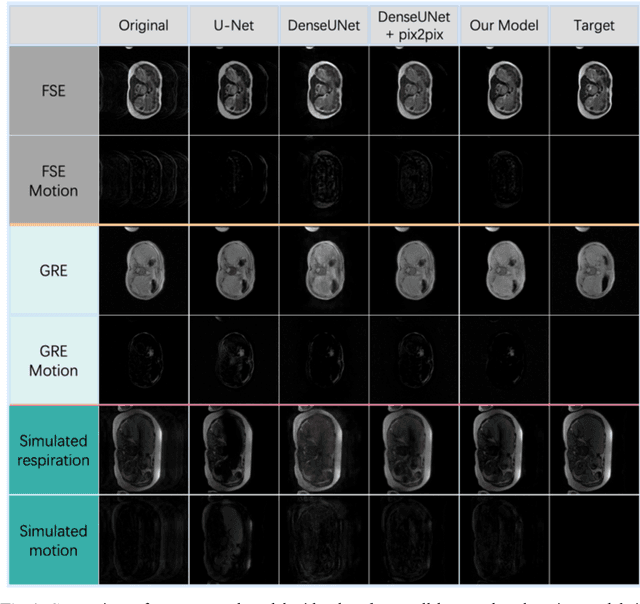

Abstract:Abdominal magnetic resonance imaging (MRI) provides a straightforward way of characterizing tissue and locating lesions of patients as in standard diagnosis. However, abdominal MRI often suffers from respiratory motion artifacts, which leads to blurring and ghosting that significantly deteriorate the imaging quality. Conventional methods to reduce or eliminate these motion artifacts include breath holding, patient sedation, respiratory gating, and image post-processing, but these strategies inevitably involve extra scanning time and patient discomfort. In this paper, we propose a novel deep-learning-based model to recover MR images from respiratory motion artifacts. The proposed model comprises a densely connected U-net with generative adversarial network (GAN)-guided training and a perceptual loss function. We validate the model using a diverse collection of MRI data that are adversely affected by both synthetic and authentic respiration artifacts. Effective outcomes of motion removal are demonstrated. Our experimental results show the great potential of utilizing deep-learning-based methods in respiratory motion correction for abdominal MRI.